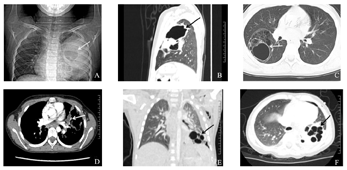

4例患儿均行胸部X线及肺部CT扫描(表3,图1),4例X线胸片提示存在感染性病变,2例X线发现囊样改变。4例CT均发现多个囊性病变,3例测量最大囊直径均>20 mm,最大者直径约40 mm;1例最大囊直径<20 mm,病变均局限于单一肺叶;其中1例患儿初次报告提示存在左侧肺脓肿,抗感染治疗后复查CT发现囊性病变。1例CT平扫发现感染性病变伴多发囊腔,建议CT增强除外肺隔离症。2例患儿进行CT增强扫描未见明显异常强化灶,显示病变组织为肺动脉供血。

A:胸部X线提示左肺上野可见一类圆形囊性透亮影;B:CT矢状位示左上肺多发囊性透亮区,可见液气平面;C:CT水平位示右下肺多房囊实性肿物;D:CT增强扫描可见囊性部位为肺动脉供血,箭头所指为肺动脉;E:CT冠状位示左肺下叶大片实变,内见多发小囊状透亮影;F:CT水平位示左肺下叶多发薄壁小囊状透亮影。